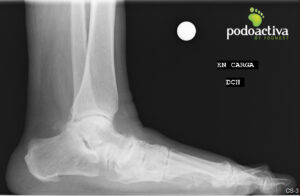

Mujer de 70 años acude refiriendo molestias a nivel del arco interno con evolución de 7 meses y no mejora con reposo ni antinflamatorios.

Se observa pie plano grado IV y lesión del ligamento de Spring. Se realiza exploración biomecánica y se observa una marcha en supinación compensando las molestias del arco interno. Tras el test biomecánico, indican alteraciones en la articulación subtalar y en los elementos estabilizadores del arco plantar.

Finalmente, el diagnóstico es un pie plano adquirido del adulto que cursa con lesión del ligamento de Spring y alteración del músculo tibial posterior.